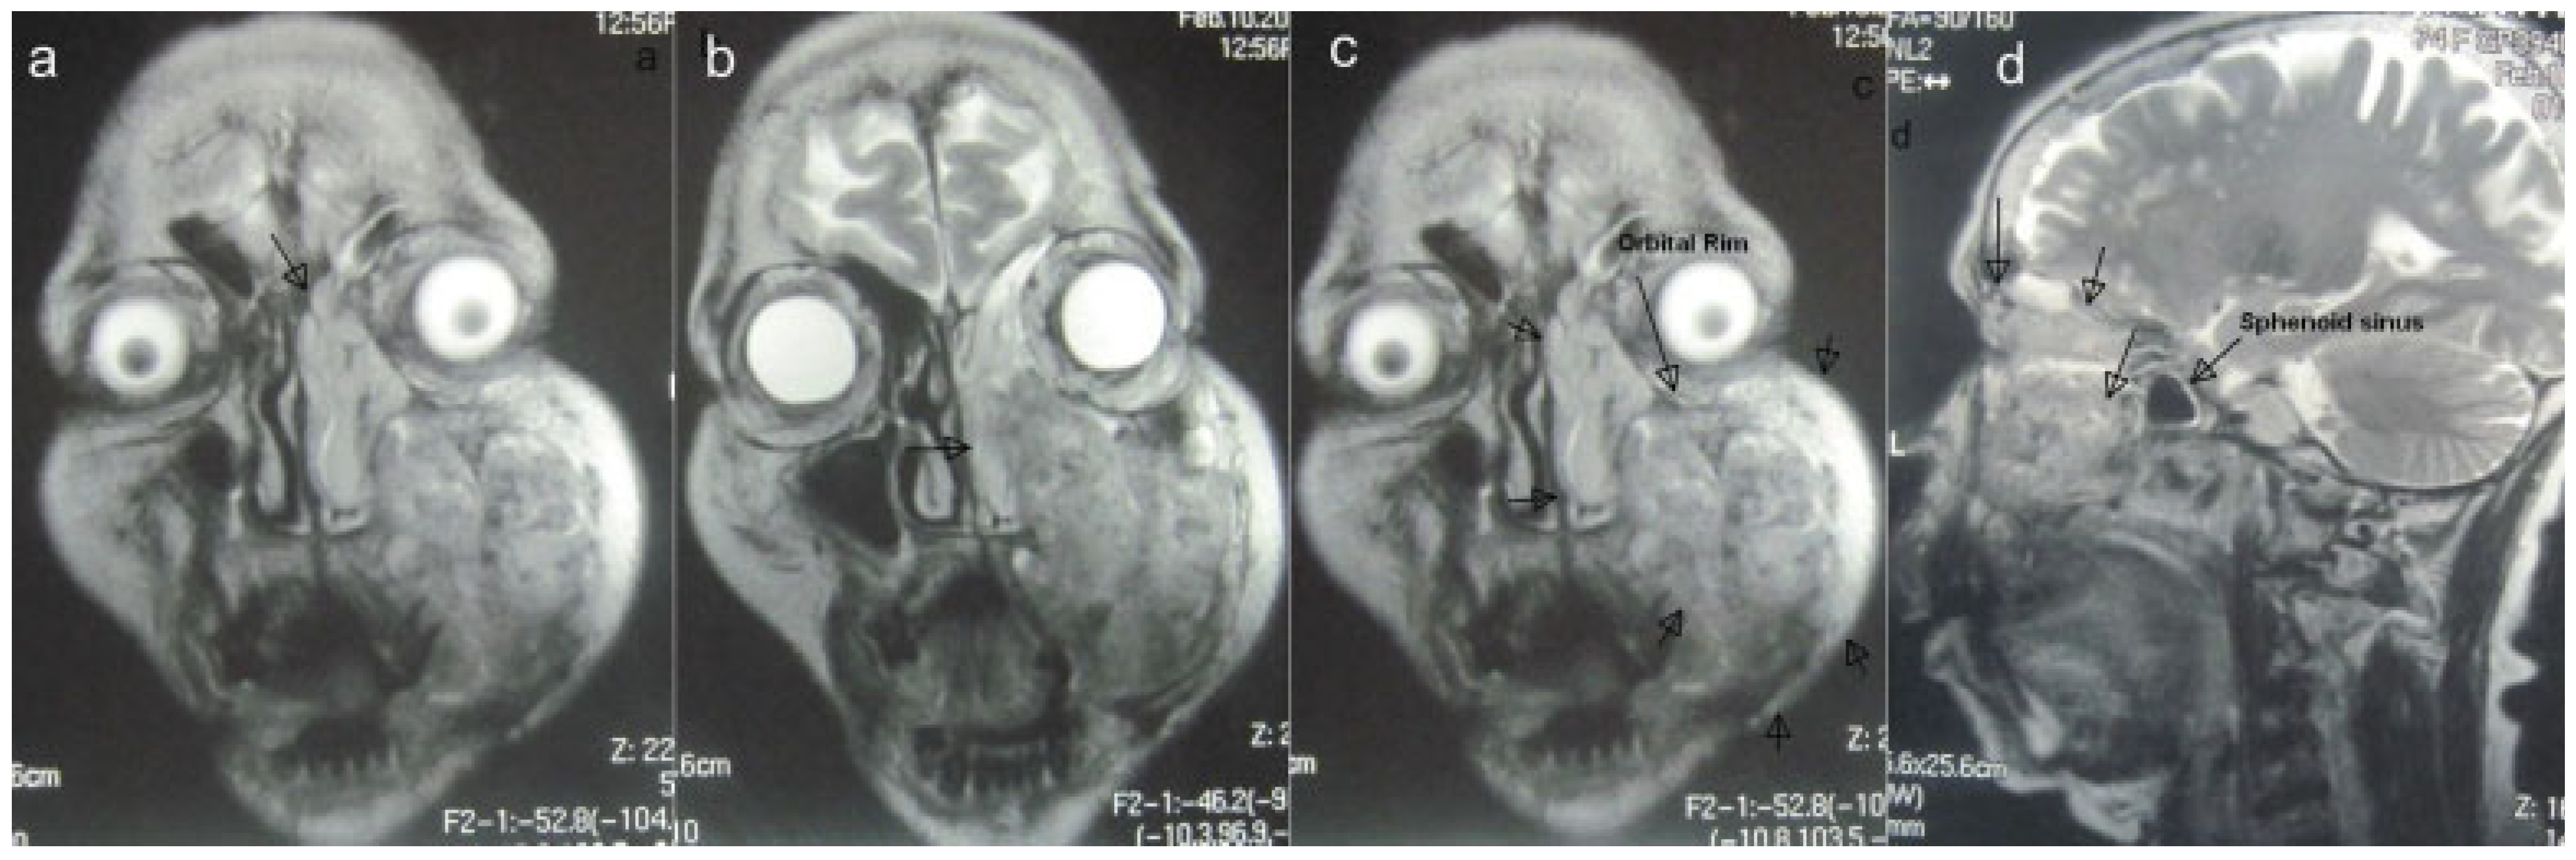

Imaging studies included an orthopantomograph and magnetic resonance imaging (MRI; Figure 2A–D), which revealed a destructive lesion involving the maxillary basal bone, the maxillary sinus with breach of its walls, and the left anterior and posterior ethmoidal air cells that crossed the midline without involvement of the cranial cavity. A metastatic workup included bone scanning, which revealed no evidence of metastasis. The floor of the left orbit was abutted but not breached.

Figure 2. (A to D) Magnetic resonance images: coronal and sagittal views indicating extent of lesion (arrows).